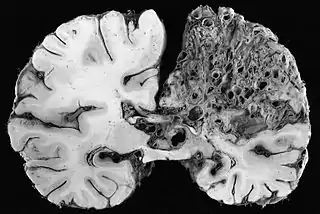

![]() Vista macroscópica de malformación arteriovenosa en el lóbulo parietal. | ||

La malformación arteriovenosa cerebral o MAV es una patología vascular congénita. Se trata de arterias anormalmente dilatadas que desembocan directamente en venas también anómalas (arterializadas), sin la interposición normal de una red capilar entre ellas,[1] sustituyéndose al capilar por un ovillo enmarañado de vasos sanguíneos irreconocibles; por lo que el paso de sangre desde la arteria a la vena se hace de una manera muy veloz, haciendo que la vena se dilate y corra el riesgo de romperse. Tienen el aspecto de una masa retorcida de tamaño anormal y un color grisáceo. Son lesiones muy poco comunes, ya que ocurren en menos del 1% de la población (3 de cada 10000 personas). Se presenta más comúnmente entre los 15 y 20 años, aunque también puede manifestarse posteriormente.[2]